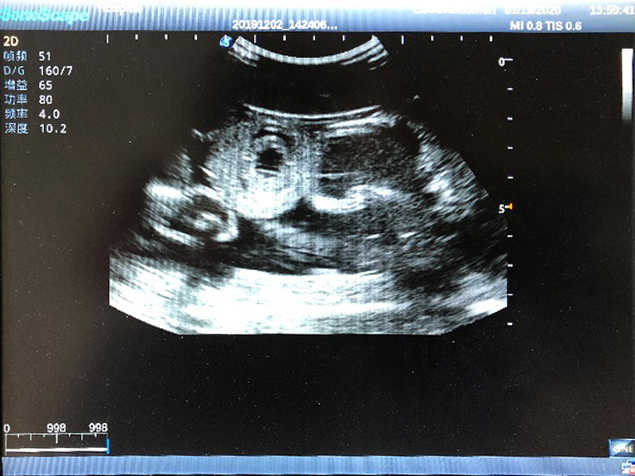

2)  High quality ultrasound image with clear structures like gallbladder, liver, intestines, arteries and veins etc.

3)  Compatible with all types of clinical ultrasound machines

4)  ltrasound gallbladder pathologies like cholecystitis, gallstone and polypoid degeneration

5)  Normal & pathological ultrasound live and intestine models inside

6Durable for repeated use & easy replacement for consumable parts